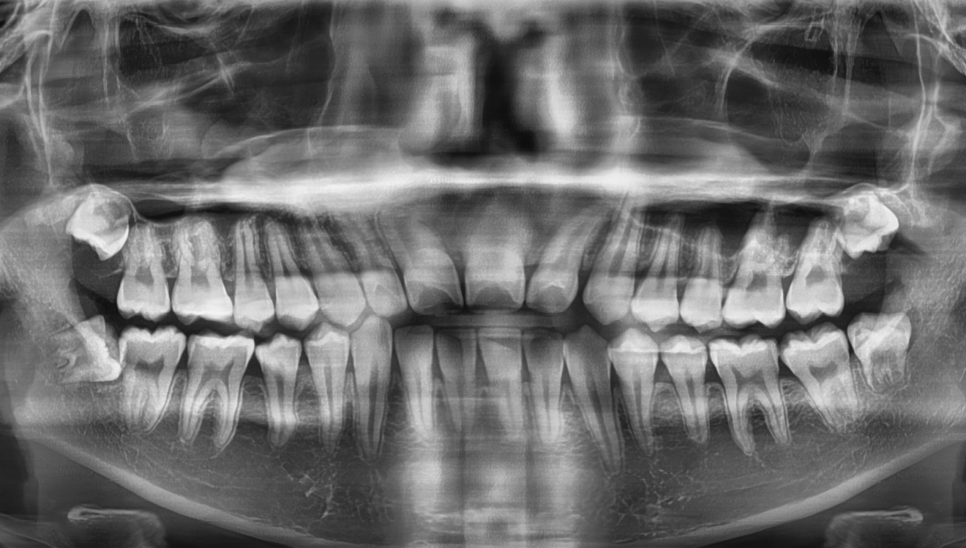

싱가폴에서 유학중인 10대 후반의 분이였어요.

현지 의사가 검진을 해주다가 사랑니를 발견했고,

뽑을 거면 한국 들어갔을 때

강남레옹치과로 가서 뽑으라는 말씀을 들으셨대요.

엑스레이를 더 자세히 보면

나이가 어려서 그런지

사랑니도 완전히 자라지 않은 상태입니다.

근데 뽑아도 될까요??

네! 문제가 될 가능성이 있다면

발치는 빠르면 빠를수록 좋습니다!

반대쪽과 다르게 누워서 자라고 있는 거 보이시죠??

지금도 잇몸에 불편감을 주는데

앞으로도 계속 염증을 일으킬 케이스!